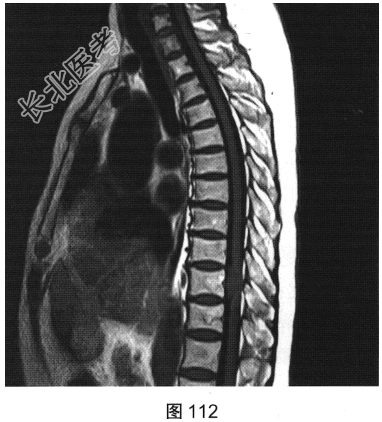

- [材料题] 患者女性,59岁,无明显诱因出现腰背部疼痛伴双下肢麻木1年,久行、久坐、久站或咳嗽、排便时疼痛加重,休息后症状缓解,1个月前腰背部麻木疼痛突发加重,行走100米既感疼痛难忍,伴双下肢无力疼痛。查体:脊柱无明显侧弯,相当于T₁₀平面以下感觉减退,腰椎活动度受限,无紧张,棘突旁压痛、叩痛,向双下肢放射。挺腹试验阳性,跟臀试验(+),双侧直腿抬高试验(一),双下肢小腿外侧、足背感觉稍差,双侧

背伸肌肌力4级;肌张力正常,双侧巴宾斯基征可疑阳性。实验室检查:人类白细胞抗原B27阴性(一),RF<10U/ml(正常值0~15U/ml)。

- 简答题2、患者行MRI检查,如图111~图114所示。根据患者病史及影像学检查,请问其最可能的诊断是什么?